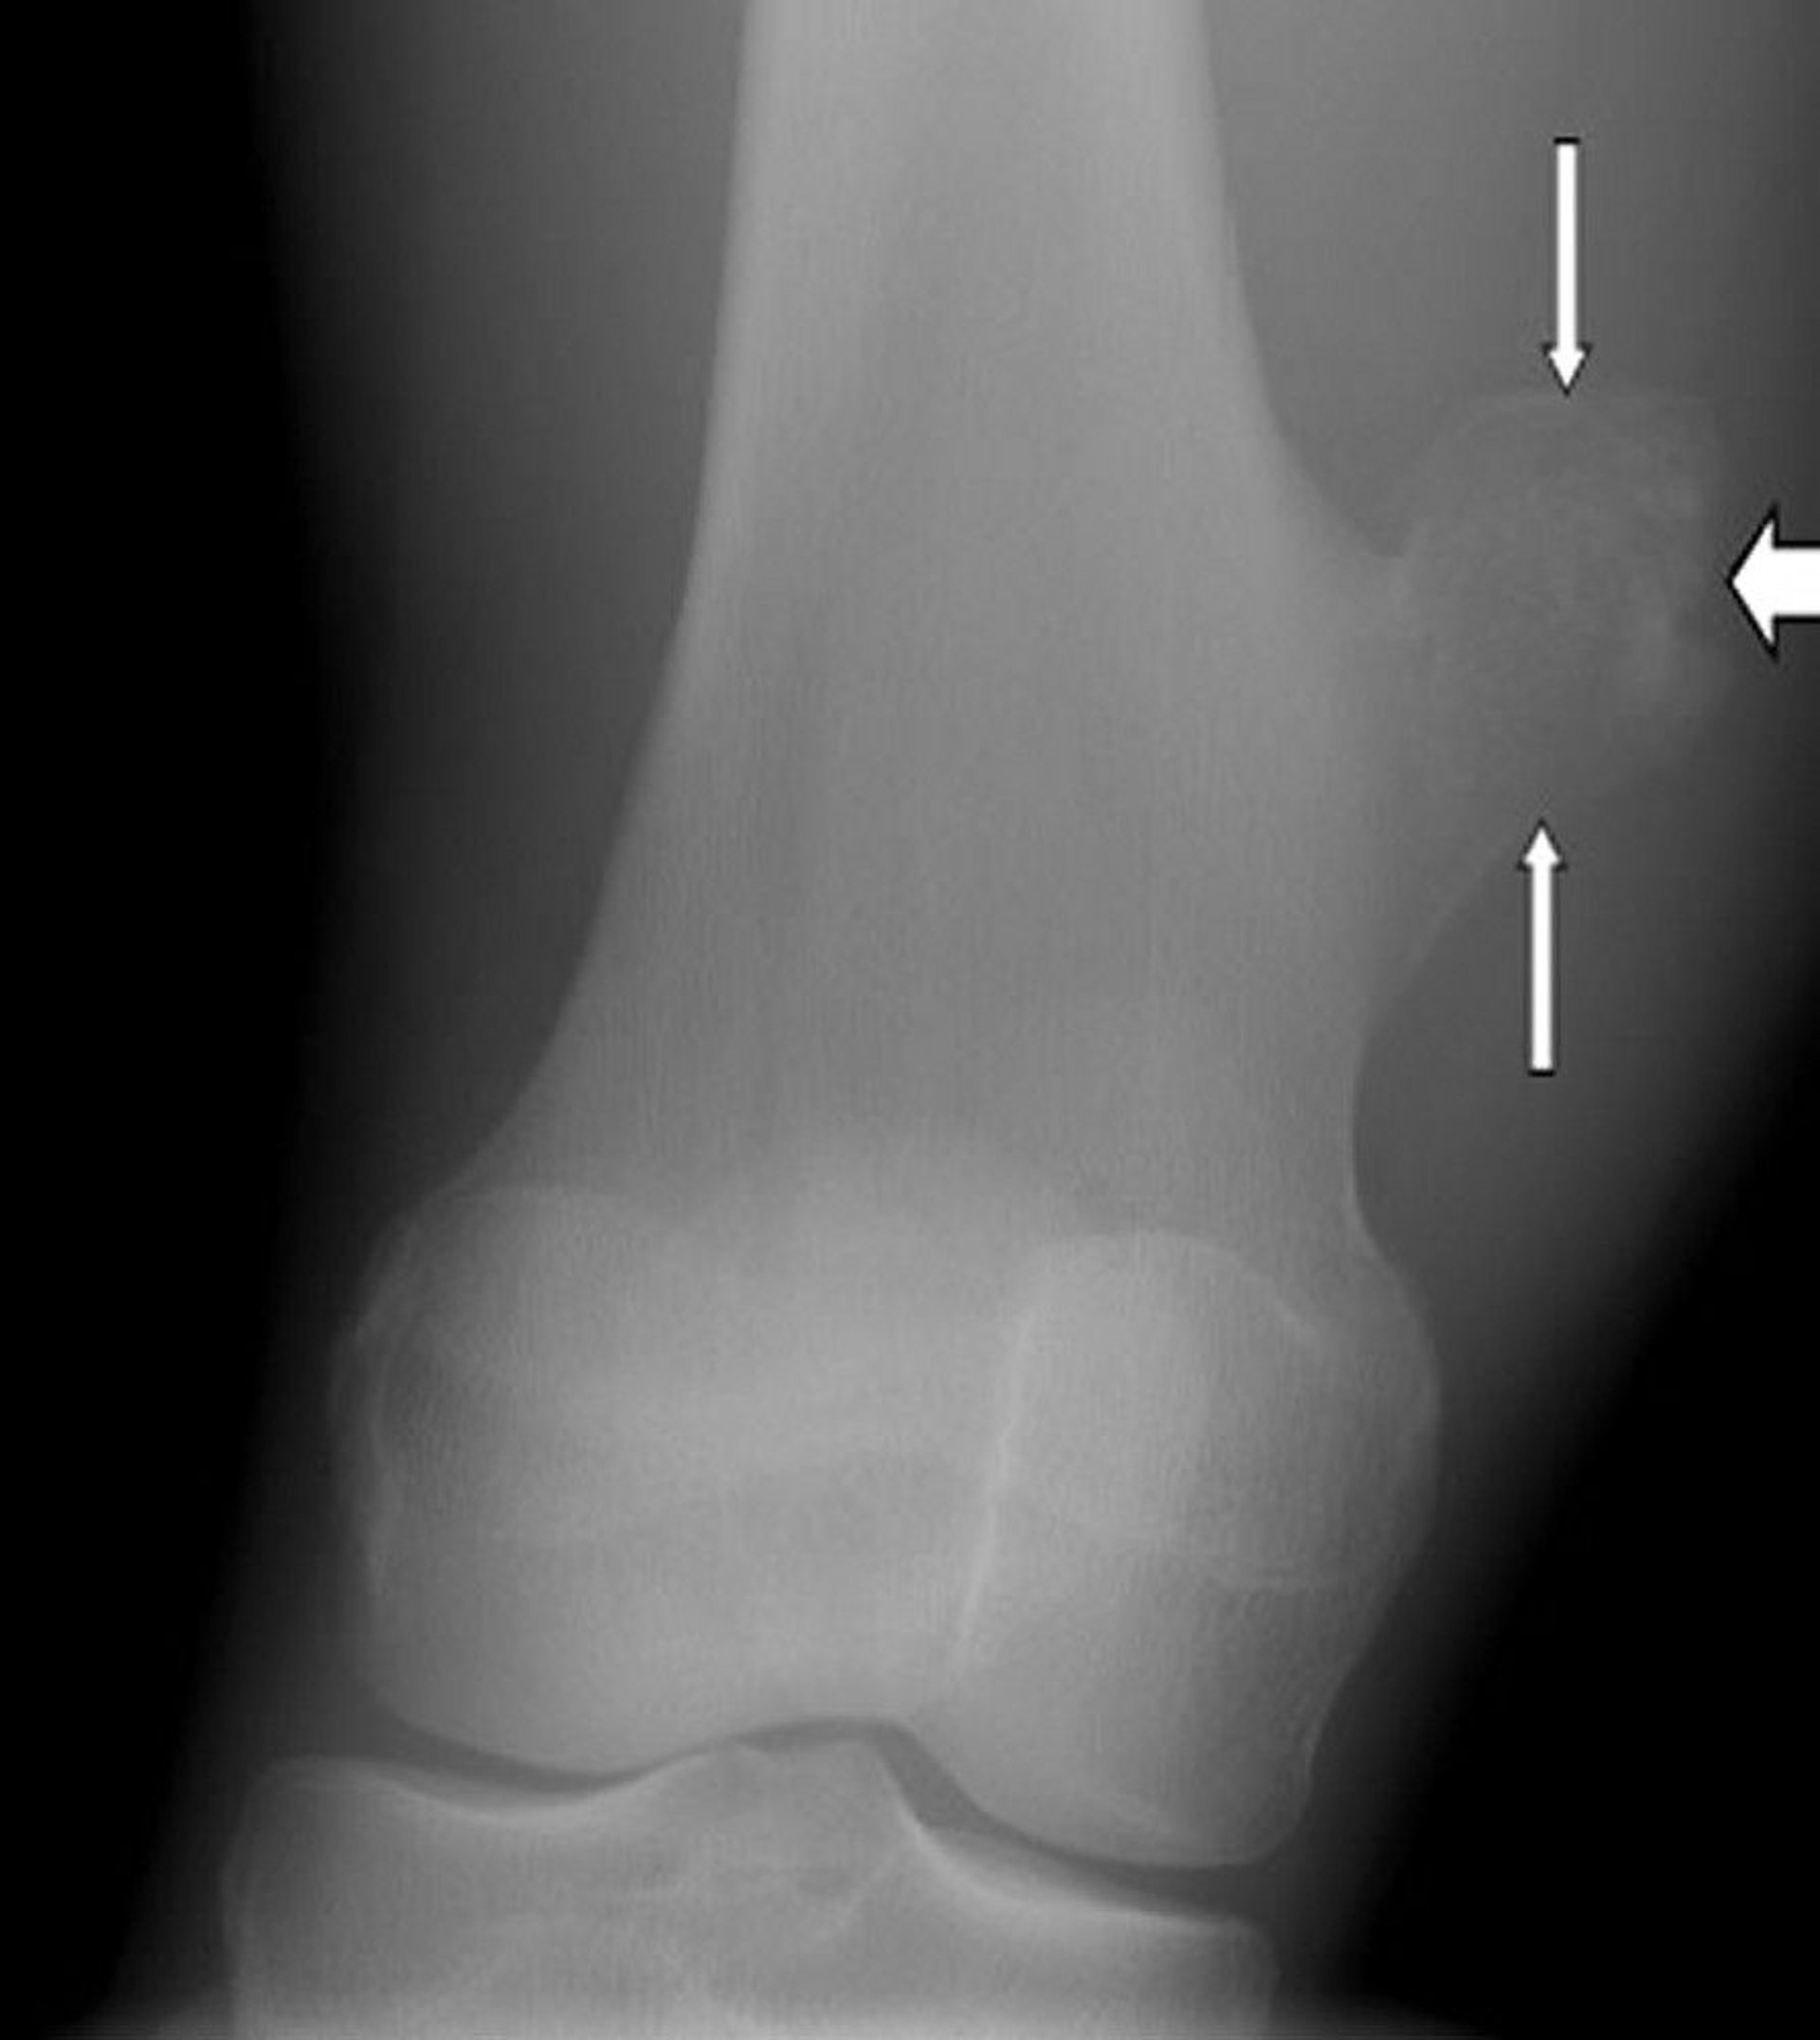

Pemeriksaan sinar-x pada lutut ini menunjukkan osteokondroma, yaitu pertumbuhan pada permukaan tulang paha (panah) di atas sendi lutut.

Gambar milik Michael J. Joyce, MD, dan Hakan Ilaslan, MD.